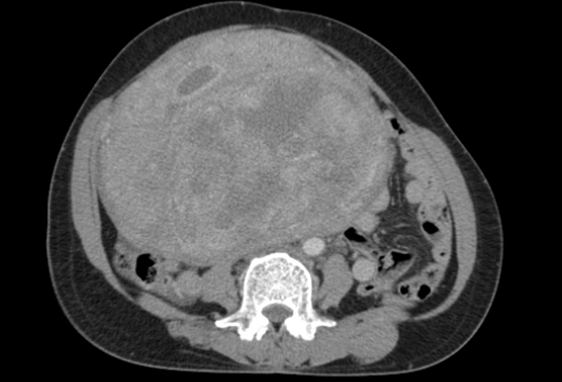

Phẫu thuật cho bệnh nhân mang khối u cổ tử cung nặng 7kg ảnh 1Phim X-Q khối u. (Ảnh: PV/Vietnam+)

Kết quả chụp cắt lớp vi tính ổ bụng cho thấy vùng tiểu khung lệch trái có khối tỷ trọng kích thước 26x15x18 cm phát triển lên phía trên bên phải ổ bụng, đè đẩy các quai ruột, ngấm thuốc sau tiêm kèm theo vôi hóa và có dịch trong khối, kèm theo hạch nhỏ lân cận.

Các bác sỹ chẩn đoán khối u lớn tiểu khung theo dõi u xơ tử cung kích thước lớn hoặc u quái buồng trứng phải.